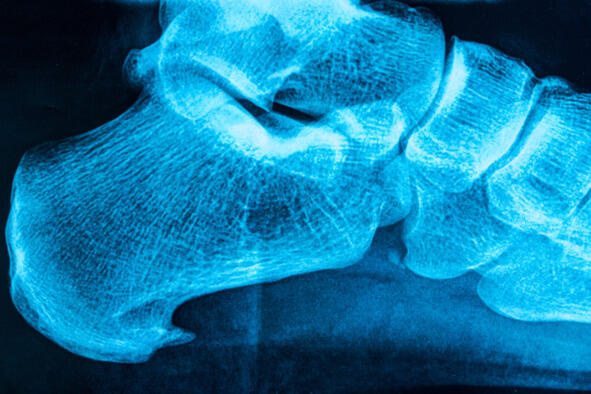

Пяточная шпора (плантарный фасциит)  это заболевание, которое связано с воспалением мышц, связок и сухожилий в области пятки из-за разрастание костной ткани в виде шипа.